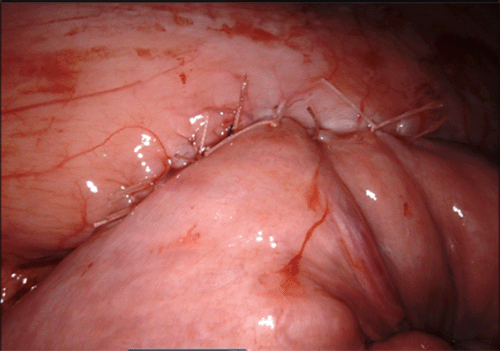

The suture line was oversewn with interrupted 3-0 Vicryls in a Lembert fashion, including two sutures proximal to the anastomosis to elevate the jejunum and prevent any kinking at its entry point along the mesentery (Figure 8).

Figure 8. Interrupted 3-0 Vicryls in a Lembert Fashion. Published with Permission